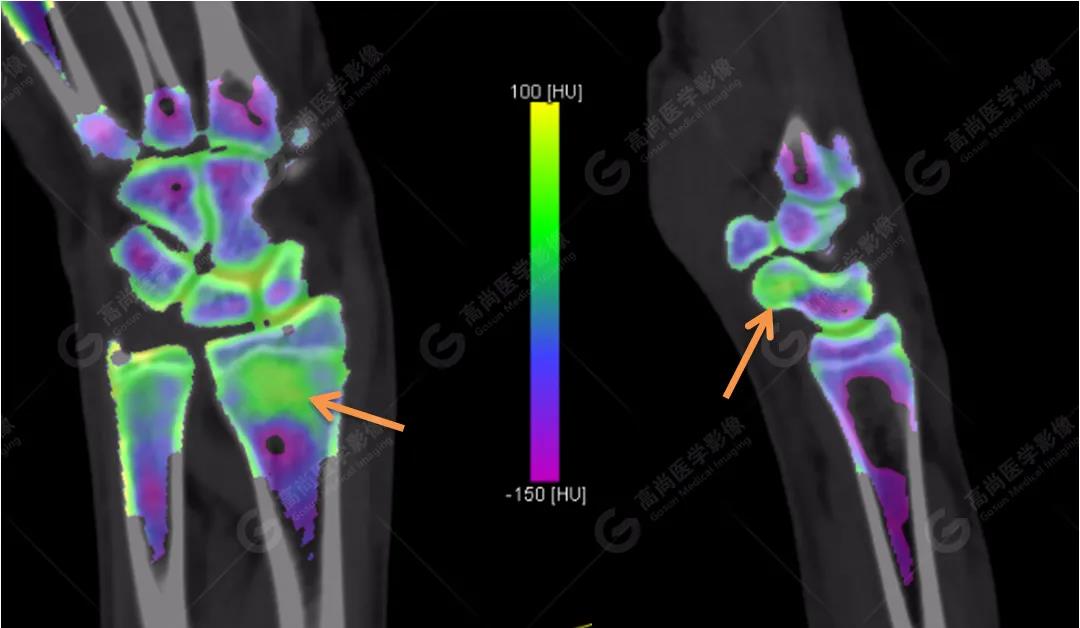

3、雙能CT骨髓成像(雙能虛擬去鈣圖像)

高尚醫(yī)學影像診斷中心的Flash雙源CT可以利用雙能量骨髓成像來顯示骨骼內的骨髓水腫,而外傷性的骨髓水腫往往提示骨挫傷或小梁微骨折。重建一下雙能虛擬去鈣骨髓圖像,進一步排除骨挫傷、微骨折。

雙能CT骨髓成像圖上發(fā)現(xiàn)了左側橈骨遠端和右側舟狀骨骨髓水腫(箭頭所示),進一步查體這兩處骨髓水腫剛好與患者的局部壓痛點相一致。